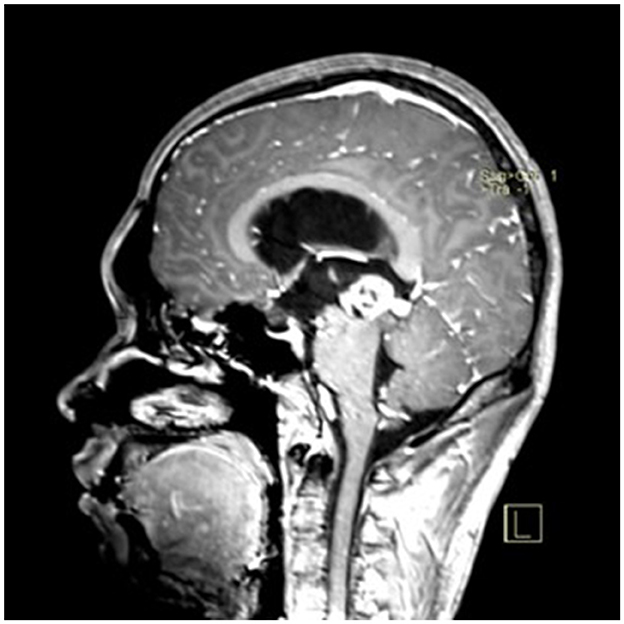

A 22-year-old male presented with intermittent dizziness and headache lasting for 2 weeks. MRI at admission revealed a cystic mass in the pineal region, accompanied by supratentorial hydrocephalus (Figures 3–5). No surgical contraindications were identified. After discussion with the patient's family, neuroendoscopic resection was performed via the Transfrontal-Transventricular-Transforaminal Approach. Intraoperatively, a 20 × 20 mm soft, well-vascularized tumor was found obstructing the cerebral aqueduct. The lesion had well-defined margins and was carefully dissected from surrounding adhesions, preserving adjacent veins and brain tissue. Macroscopic total resection was achieved en bloc (Figures 6–8). Postoperative day 1 MRI confirmed complete tumor removal and resolution of hydrocephalus (Figures 9–11). Postoperatively, no complications were observed. However, due to personal reasons, the patient was discharged on postoperative day 11. Histopathology confirmed a mixed germinoma. No recurrence or surgery-related complications were noted during follow-up.

Figure 4

Preoperative contrast-enhanced MRI (sagittal view) showing the pineal region tumor.